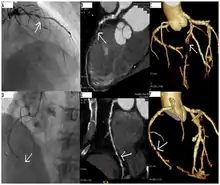

Coronary angiography of a critical sub-occlusion of the common trunk of the left coronary artery and the circumflex artery. (See arrows)

Angiography (left) and CT (middle and right) of chronic total occlusion lesions at the left anterior descending coronary artery (LAD) and right coronary artery (RCA).